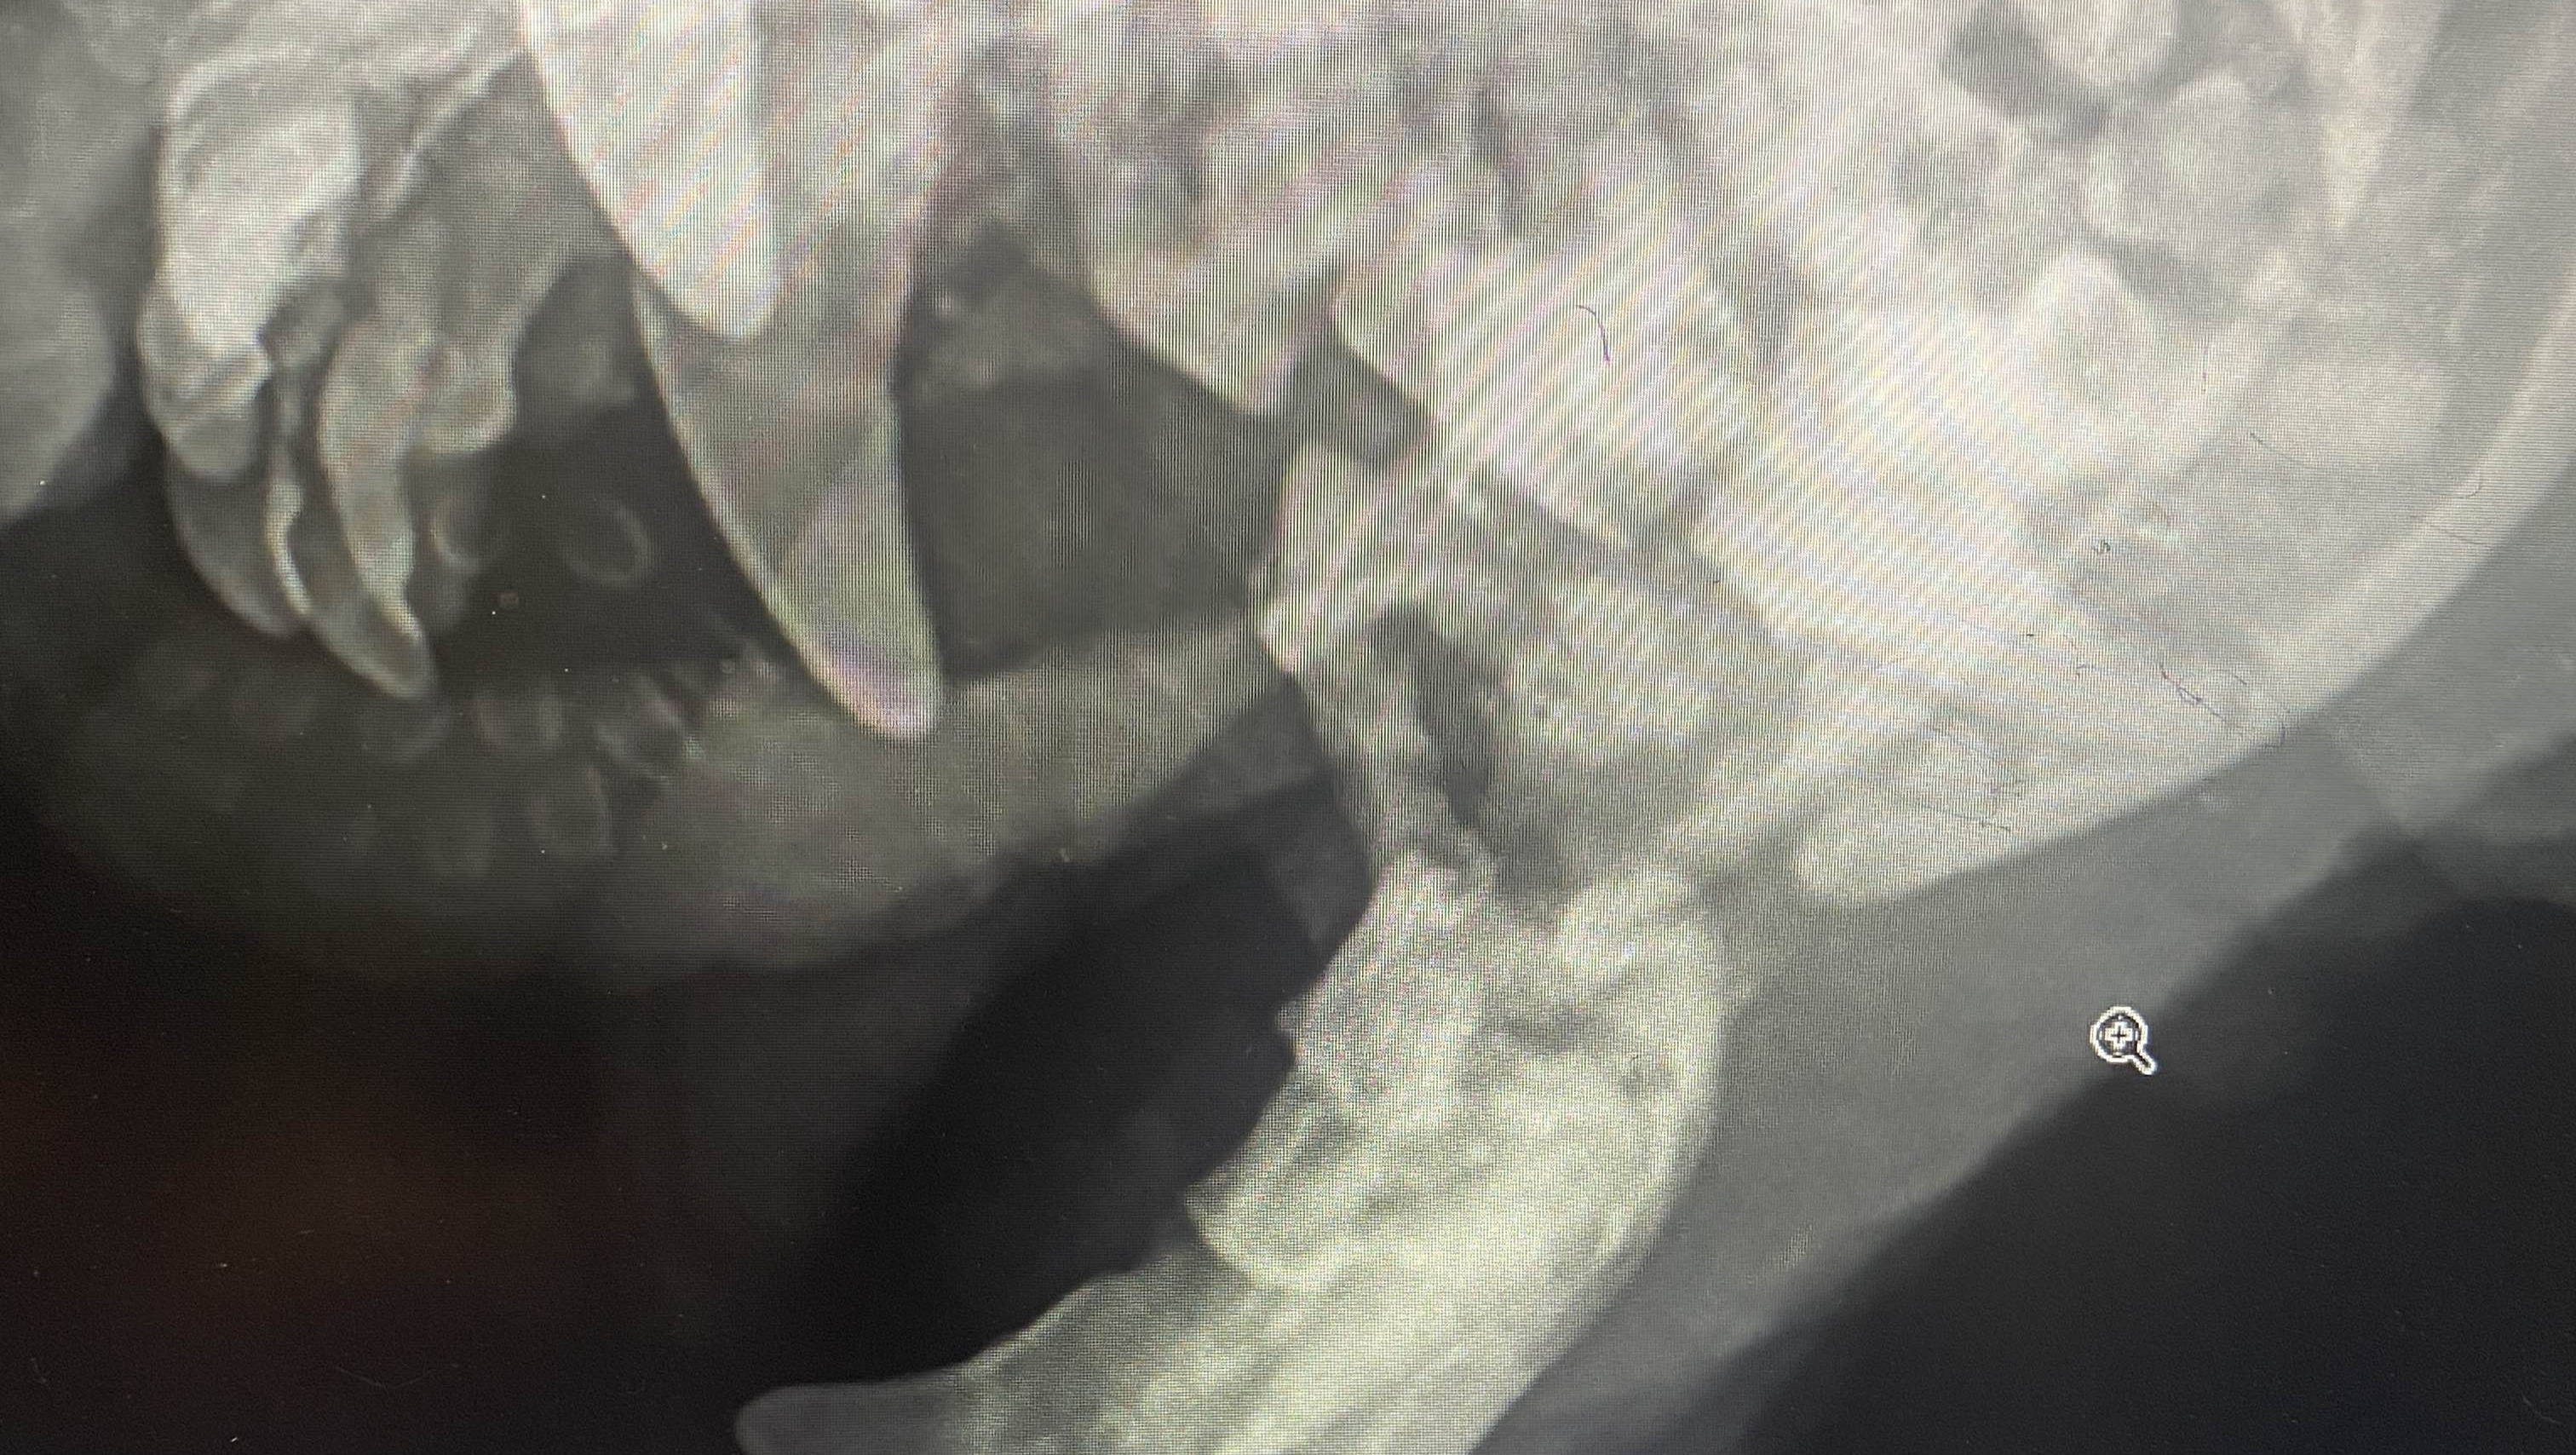

In recent days, Buster has been suffering a fractured jaw on both sides. Due to his age and dental disease, his bones became fragile, and his jaw gave out. Despite this and some noticeable discomfort, Buster still wakes every day with a wagging tail and excitement in his eyes. He hasn't given up so we refuse to give up on him.